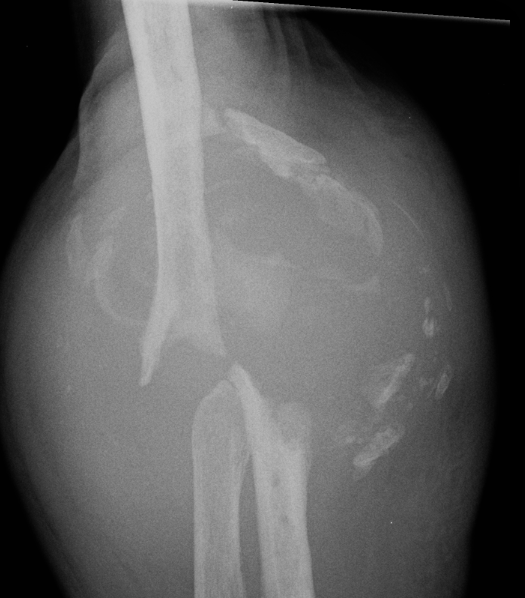

Aseptic Loosening

- systematic review of 3000 TEA

- loosening rates 10% for unlinked and 14% for linked prosthesis

Results

- revision with allograft - prosthesis composite

- 25 patients

- one nonunion / one malunion

- 84% TEA survival

Ulna allograft - prosthetic revision TEA